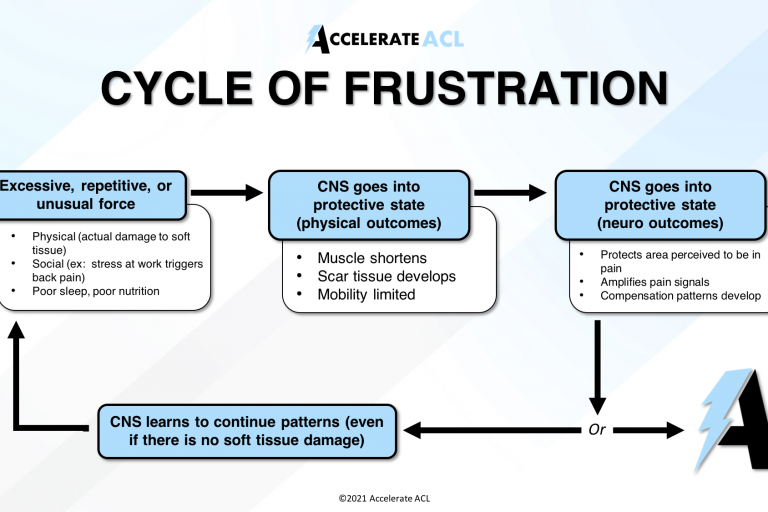

We are thrilled to share some exciting news with you! Our very own co-founder, Zach Michael, was recently featured on the esteemed Starting Block Podcast, where he delved into a comprehensive discussion about Accelerate ACL’s revolutionary approach to ACL recovery and the remarkable insights gained from working with clients who are behind schedule in their…